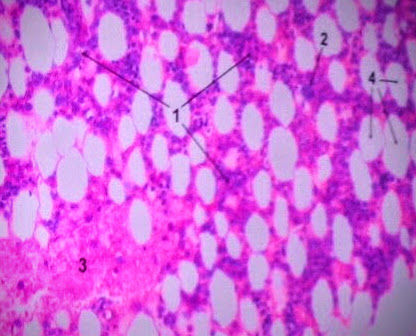

Question 6

Question

Label this image

Image:

8901a2bc-c7a0-4c65-8e2b-c87f139c1b3e (image/jpeg)

Answer

Bone Marrow